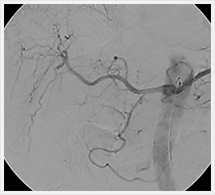

画像紹介(頭頚部血管編)

画像は、頚動脈の狭窄部分に“ステント”と呼ばれる金属性の網状の筒を留置して、血管を正常径まで拡張させる手術です。この治療は、内膜剥離術と比較して非侵襲的であり、高齢者やいろいろな合併症を持った方にも負担を少なくして行うことができます。術後の安静期間や入院期間も短いのが特徴です。